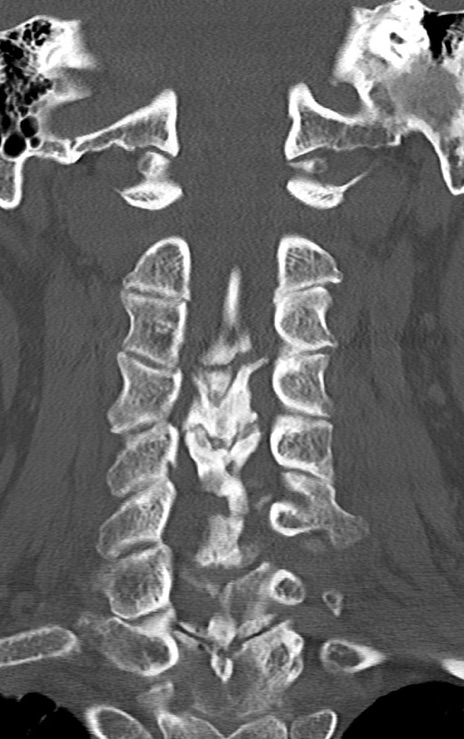

頚椎CT

矢状断像